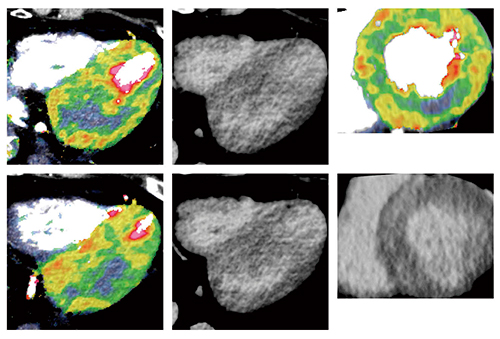

59歳,男性。非常にコントロールの悪いHTNがあり,心電図にてⅡ,Ⅲ,aVF誘導の異常Q波が認められ,心筋梗塞疑いのため当院を受診した。左冠動脈(LCA)が大きく,RCAは低形成を呈し,LAD,第1対角枝(D1),左回旋枝(LCX)に明らかな病変は認められなかった。負荷Dynamic CTPでも病変は認められなかったが,Voxel-wise MBF mapでは全周性に内膜下の血流異常が認められ(図5),微小循環異常が疑われた。遅延造影CTでは,びまん性に淡い造影が描出されている(図6 上段)。遅延造影MRIでも,びまん性の淡い造影の存在が確認され(図6 下段),本症例は高血圧心におけるびまん性の線維化と診断された。

図5 症例3:Voxel-wise MBF mapとCTAのフュージョン画像

図6 症例3:遅延造影CT(CTDE:上段)と遅延造影MRI(LGE:下段)の比較

なお,extracellular volume(ECV:細胞外容積)を計測したところ,MRIでは35.1%,CTでは36.5%との結果であった。ECVは,MRI領域において,心筋性状を判定するツールとして非常に期待されており,多くの研究が行われている。しかし,MRIでECVの測定を行う場合,MOLLI法などによるT1計測を1スライスごとに行う必要があり,不整脈や心拍数の影響でT1計測の精度が低下することがある。一方,CTでは遅延相の画像から造影前の画像を差分することで簡単に内腔と心筋の造影剤濃度比が算出され,それをヘマトクリットで補正することでECVを求めることができる。われわれの経験では,不整脈のある症例ではCTの方がMRIよりも安定的にECVを得られる。

当院にて,虚血性心疾患を疑ってCT検査が行われたが結果的に正常だった症例を対象に,年齢とCTで求めたECVとの相関を見たところ,年齢が上がるにつれてECVが上昇する傾向が認められた3)。加齢によるECVの上昇は過去のMRIを用いた研究でも報告されており,CTによってECVをかなり正確に計測できていると思われる。なお,正常例のECV値は22〜30%程度に分布しているが,本症例のECV値はそこから大きく外れており,ECVからもびまん性線維化の存在を診断できる。